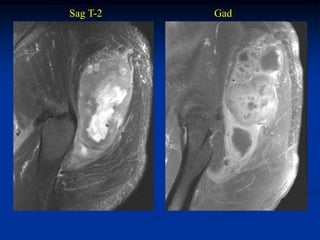

Case #250.3      Sag T-2                 Sag Gad

15 year female with painful enlarging desmoid past 6 months

while on chemotherapy

Coronal Gad shows minimal response to chemotherapy